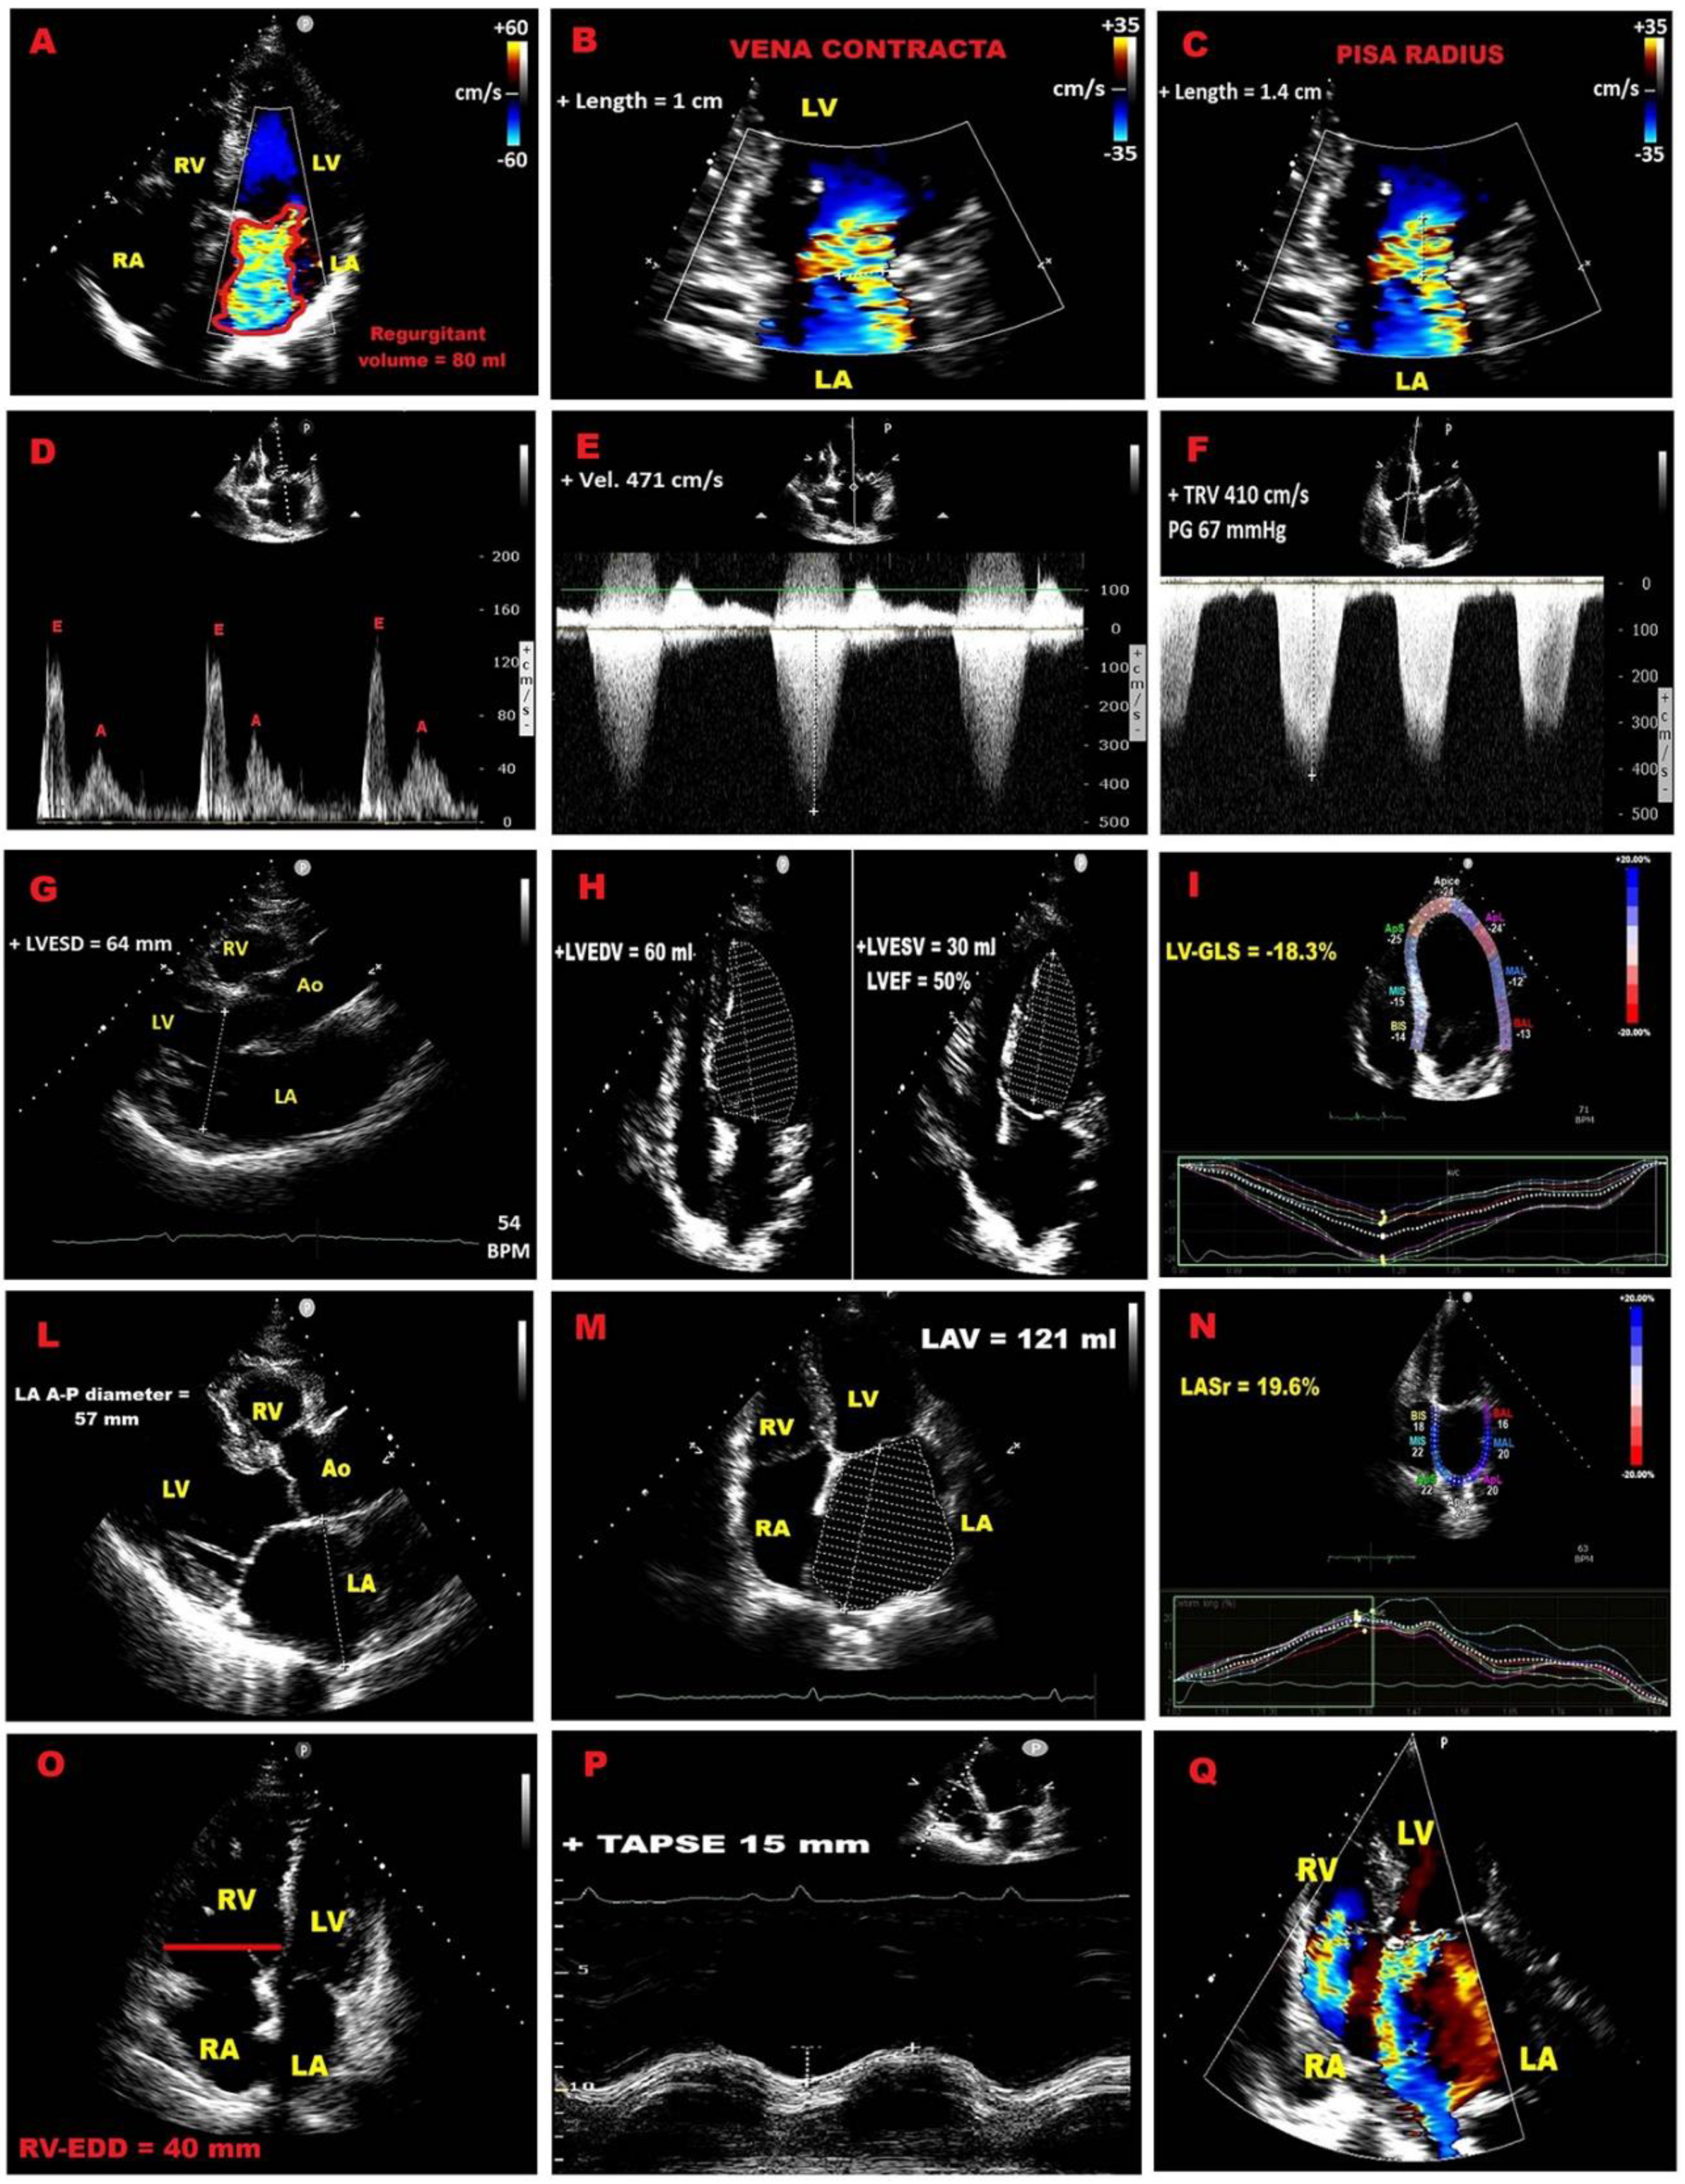

| Category | Criteria |

| Qualitative | MV morphology (flail leaflet, papillary rupture, severe retraction, perforation); Large central jet (>50% LA) or eccentric jet; Large systolic flow convergence; Dense holosystolic CW Doppler jet |

| Semiquantitative | Vena contracta ≥7 mm; Systolic pulmonary vein flow reversal; Dominant E–wave (>1.2 m/s); TVI mitral/TVI aortic >1.4 |

| Quantitative | PISA radius ≥1 cm; EROA ≥40 mm²; Regurgitant volume ≥60 mL/beat; Regurgitant fraction ≥50% |

| Structural | LVESD ≥40 mm; LA diameter ≥55 mm or volume ≥60 mL/m² |